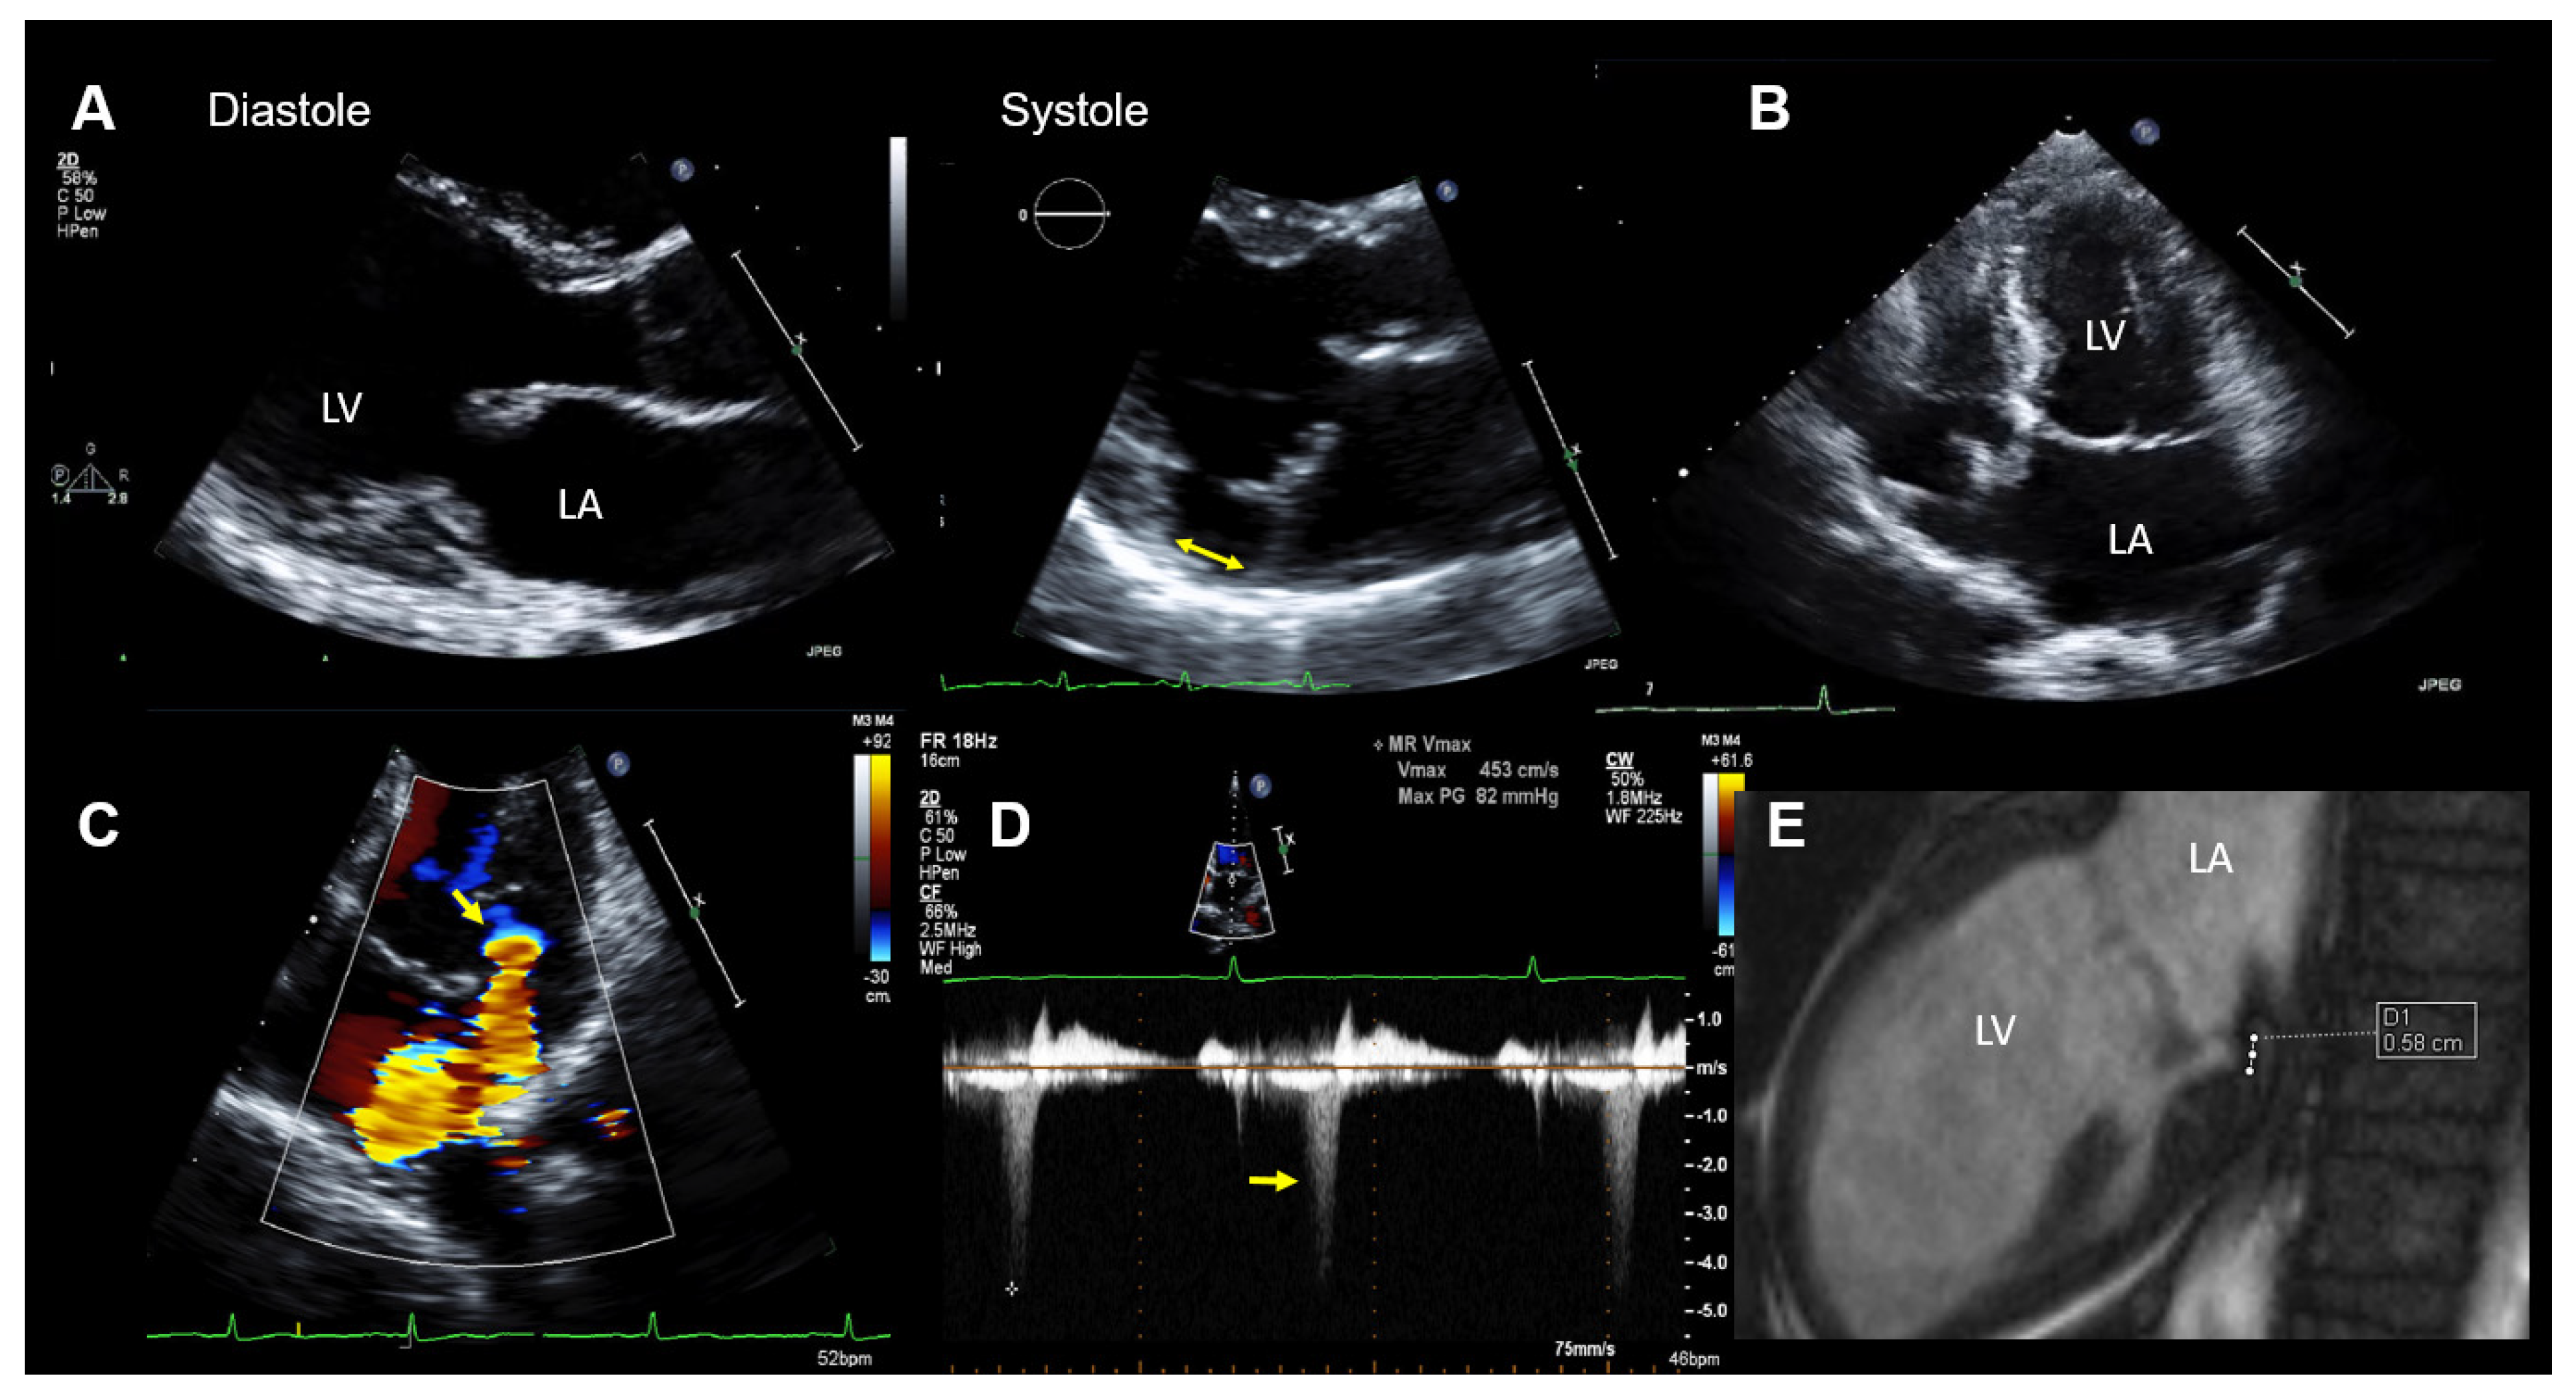

When 2D TTE imaging is used, a MAD is assessed by measuring the distance from the site of the posterior leaflet insertion into the left atrial wall (upper border of the disjunction) to the connection between the left atrium and the ventricular myocardium (lower border of the disjunction). This should be performed in a parasternal long axis TTE view at end-systole (see, also, Figure 2A and Figure 3A). Carmo et al. found a MAD prevalence of 55% (21/38patients) in patients with MMVD and MVP examined by TTE [16].

Figure 2.

Case 1: Summary of the key findings from multimodality imaging. (A) The mitral annular disjunction (MAD) (yellow double arrow) is only visible in systole in a parasternal long-axis transthoracic echocardiography (TTE) view. (B) A mildly enlarged left atrium is seen in a 4-chamber TTE view. The MAD is not clearly visualized. (C) The proximal isovelocity surface area (PISA) zone (yellow arrow) is seen. A PISA radius of 4 mm and a vena contracta of 3.5 mm indicated nonsevere mitral regurgitation (MR). (D) MR occurs only in the late-systole (yellow arrow) in Doppler imaging. (E) The MAD is measured in cardiac magnetic resonance imaging (white dots = 5.8 mm). LA = left atrium and LV = left ventricle.

At the hospital, a physical examination was normal other than mid-systolic click and a mid-late systolic murmur upon cardiac auscultation. The ECG showed no abnormalities, except for frequent polymorphic premature ventricular contractions (PVTs). The laboratory results were within the normal limits. A TTE demonstrated normal LV size and function. The mitral valve appeared myxomatous, and bi-leaflet MVP was present. MR was purely late-systolic (which confirmed the auscultation findings), and by the multimodal quantification of MR, it was moderate. In addition, a MAD was seen. The echocardiographic findings are summarized in Figure 2.

Coronary heart disease was excluded with computed tomography coronary angiography. Due to the aborted SCD and the frequent premature ventricular contractions (PVCs) on the ECG, as well as MAD with MVP, an electrophysiological study was performed, which showed inducible polymorphic ventricular tachycardia (VT).

CMR imaging confirmed the diagnosis of moderate MR (regurgitation fraction was 24%) with mild mitral annular dilation and the presence of a MAD (Figure 2E). The overall LVEF and right ventricular ejection fraction was normal, but a mild hypokinesis of the inferolateral wall was described. In addition, late-gadolinium enhancement CMR imaging showed an increased late-gadolinium uptake in the inferior and inferolateral walls consistent with focal myocardial fibrosis.